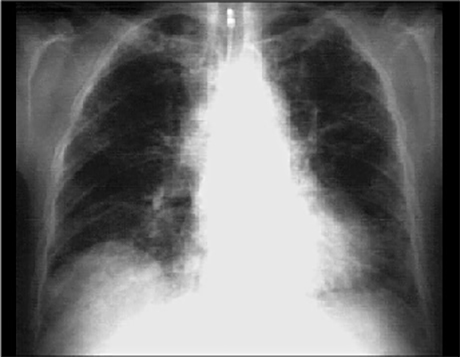

- the best interpretation of the chest X rays in our patient is right ventricular enlargement, prominent pulmonary arteries and decreased peripheral markings.

This chest X ray shows bilateral pulmonary fibrosis and mild cardiomegaly. This PA view demonstrates

increased diffuse bilateral interstitial pulmonary markings.

Note also that the

central pulmonary arteries

are prominent, compatible with pulmonary hypertension. There is mild cardiomegaly, as evidenced by a slightly increased

cardiothoracic ratio.

Note the

tracheostomy

too.